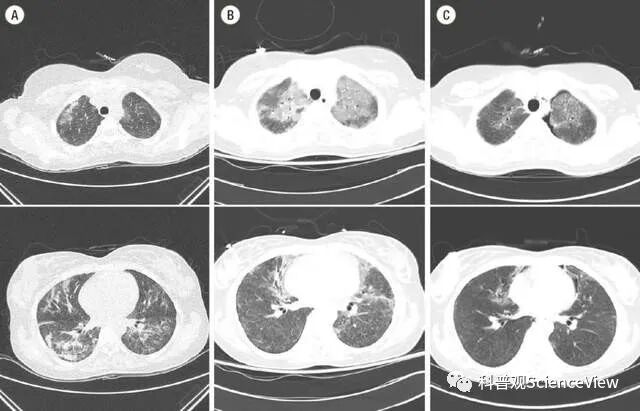

她们都是由肺炎引起了肺部纤维化症状,症状严重便会导致急性呼吸衰竭,乃至死亡的发生。

肺部纤维化